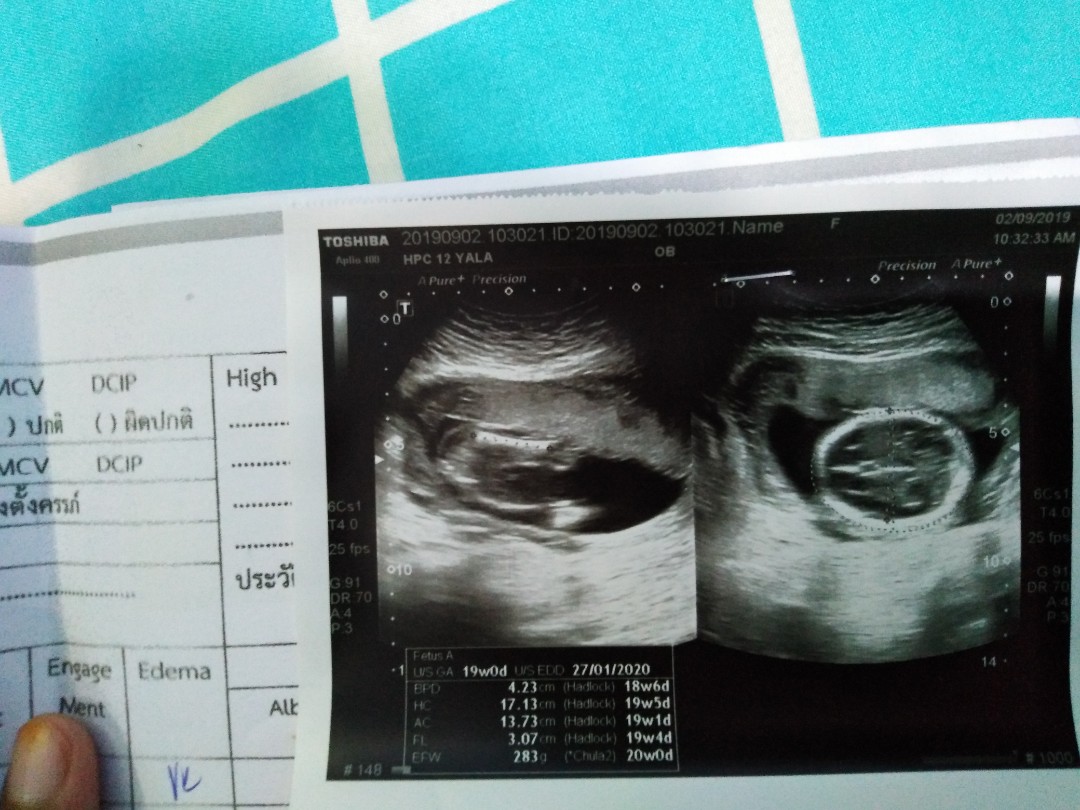

ผู้หญิงค่าา 👧 21 w